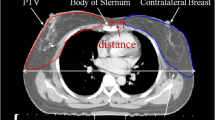

Fig. 1 supplementary material: A

dose distribution in a patient treated with PBI at the MRL. B dose distribution in a patient treated with PBI at the CTL. Structures depicted are: CTV, PTV, clips (yellow in A and blue in B), Seroma if present (in B), lungs and breasts ipsilateral and contralateral.